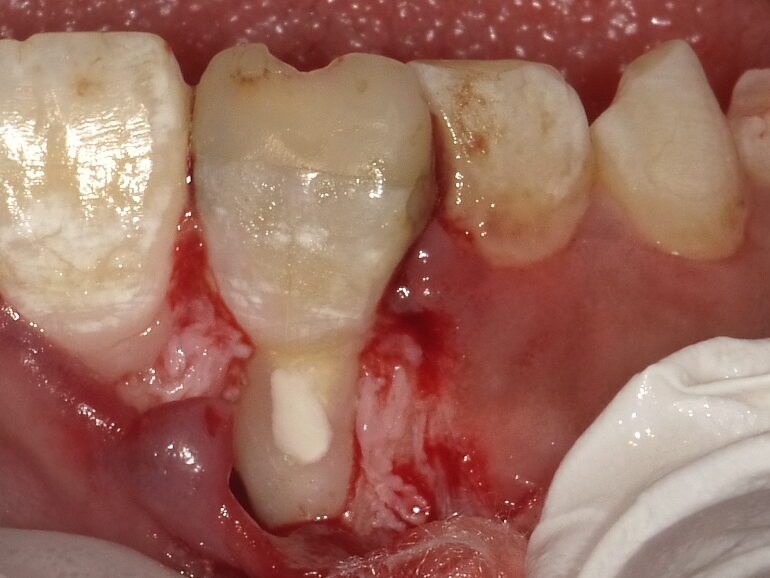

初診時の口の中とレントゲン

虫歯があるので虫歯治療をしたいと言われて当院に来られたのですが

前歯の色が黒く変色しており、前歯の上の方の歯茎が白くなっています💧

レントゲンを確認すると、根の中に詰める材料が根の中ではなく、変な位置に入っているように見えます😰

また、今はあまりしない治療かと思いますが、レジンという白い詰め物をするのに金属のピンを使って補強されているようで、その金属が透けて見えたり、中で溶けて歯が黒く変色していると思われます💦

実際の治療

外科治療(外科的歯内療法)

まずは歯の中ではなく外に出ている詰め物をとる必要があるので、外科的な治療で飛び出した詰め物を取り除くのと前の医院さんで開けられたと思われる穴を塞ぎ、その後に通常の根管治療、被せ物をする流れで治療することをお伝えしました。